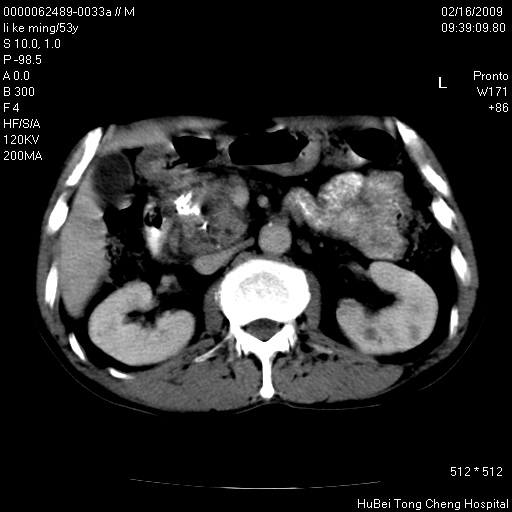

以下是引用卜一在2009-2-16 16:13:00的发言:[br]胰胆管扩张,末端明显狭窄 梗阻,胰头及十二指降段壶腹部结构紊乱。多考虑:十二指降段壶腹部癌!

以下是引用dyqct在2009-2-16 16:58:00的发言:[br]胰头内斑点状及结节状高密度影是钙化灶还是其它?以往做过什么治疗?

以下是引用zsl6918在2009-2-17 8:48:00的发言:[br]符合胰头癌侵犯十二指肠。